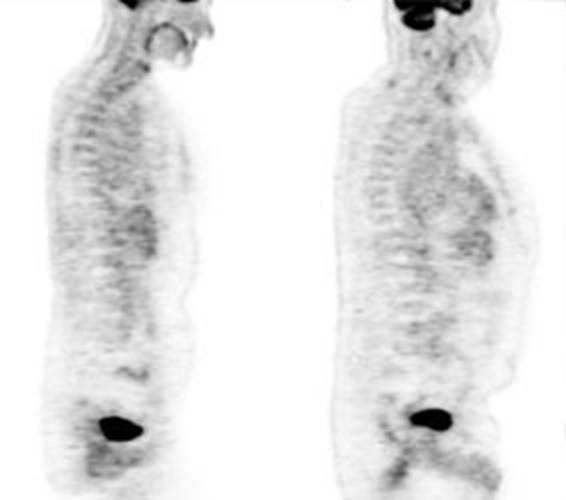

Figure 23 - Normal

thyroid activity: Symmetric

thyroid tracer uptake can be seen is some patients

Figure 24 - Normal

uterine activity: Faint

uterine uptake is common (black arrows).

Figure 25 - Normal

testicular activity: Mild

symmetric testicular uptake can be seen (black arrows)

Figure 26 - Normal

vascular activity: Faint

activity can be seen in the descending thoracic aorta (black arrows)

Figure 27 - Normal

breast activity: Faint

activity can normally be seen in the breasts (black arrows)

Figure 28 - Inflammation: The image below